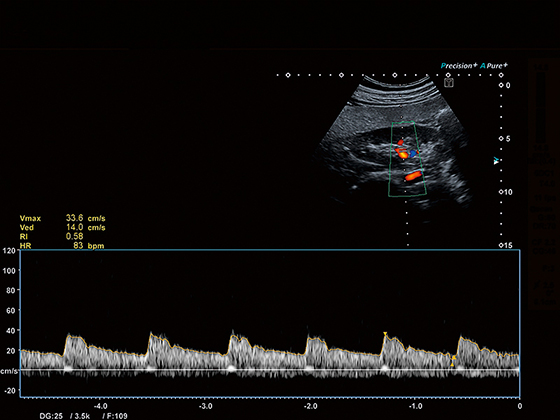

Імпульсно-хвильовий допплерівський режим

Кольорове допплерівське картування